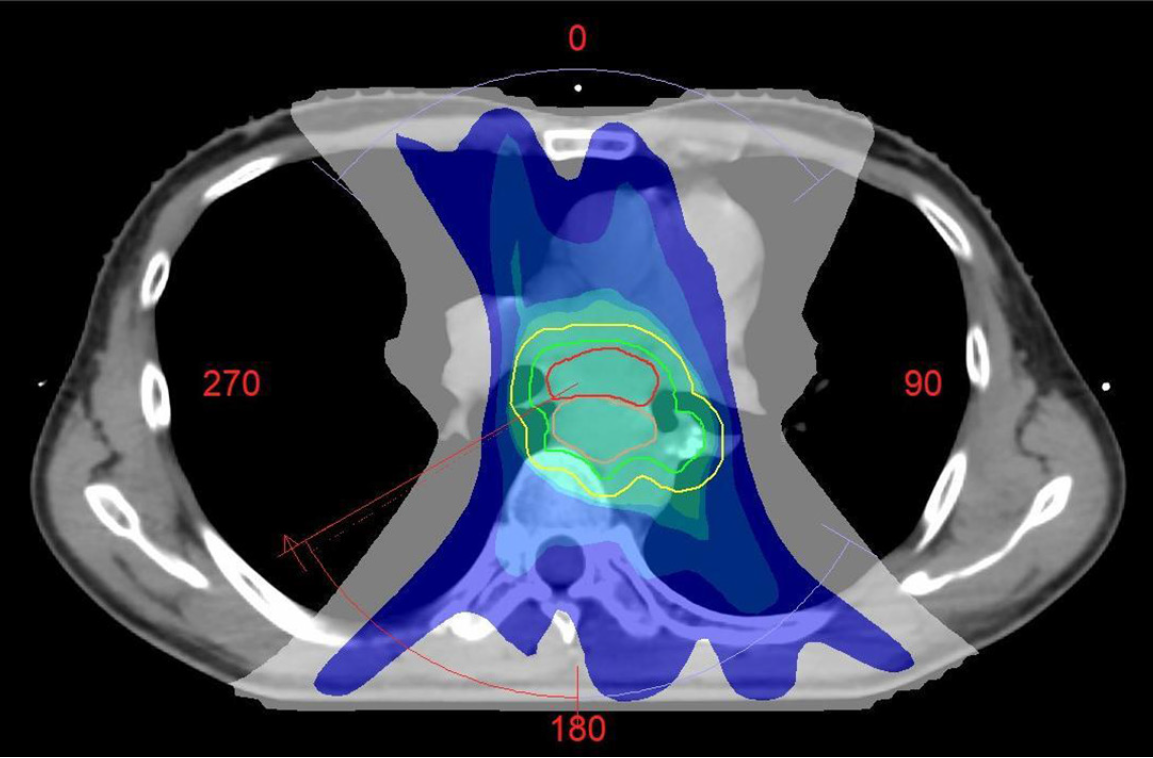

Figure 7

Radiotherapy target graph showing planning target volume.